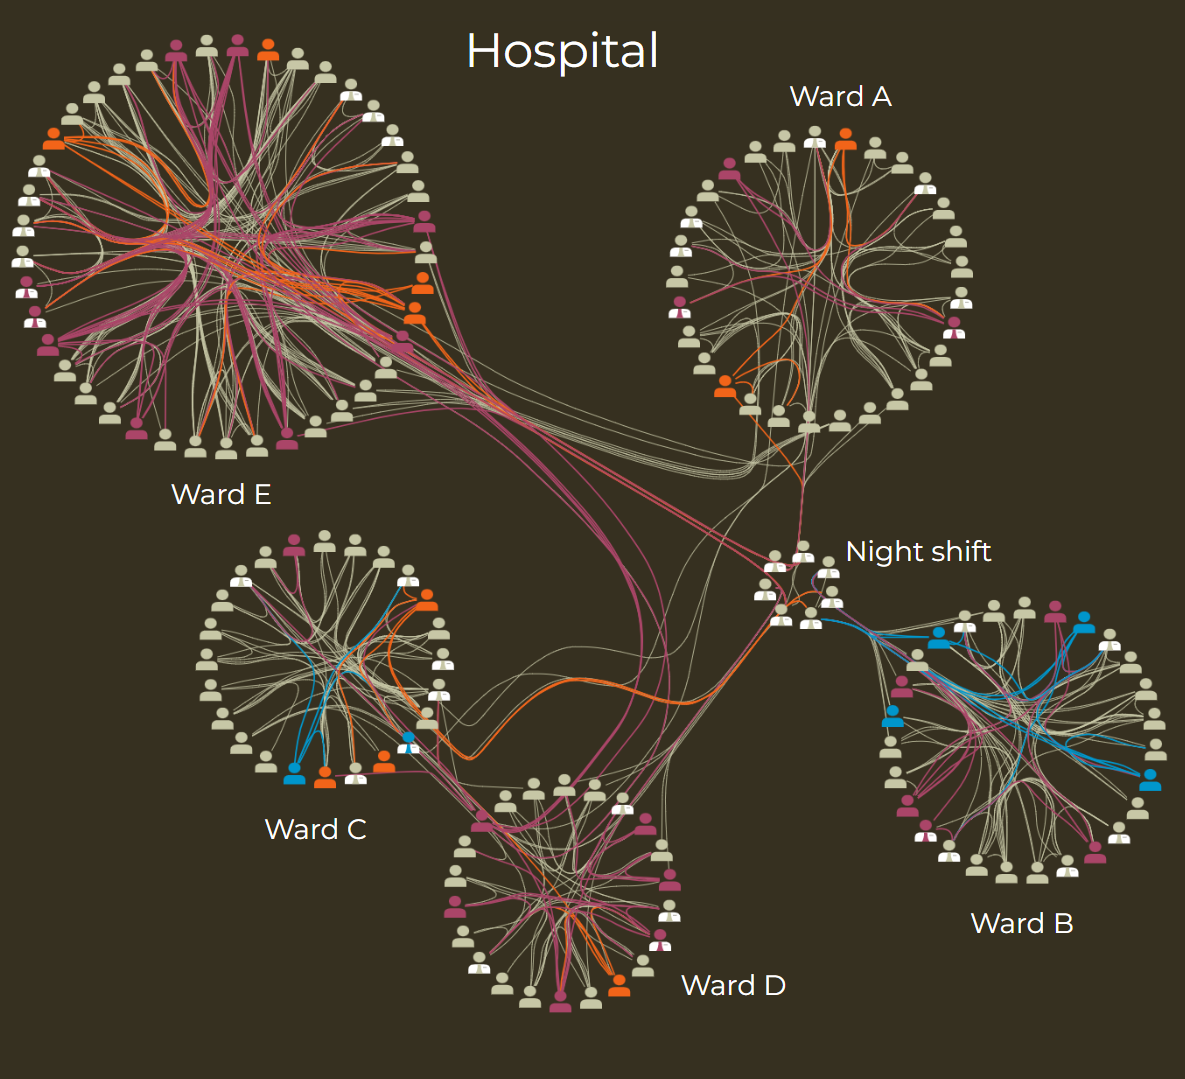

Computational biology

In fields like genetics and epidemiology, understanding relationships is key. The circular layout is ideal for visualizing protein-protein interaction (PPI) networks, gene clusters, and pathogen transmission chains. It automatically groups related entities into functional modules or outbreak clusters, making complex biological systems easier to interpret.

For instance, in a study on the hospital dissemination of Staphylococcus aureus, researchers from the University Pierre et Marie Curie in Paris used yFiles to visualize their data. The circular layout helped reveal distinct transmission clusters, supporting the analysis of how the pathogen spread.